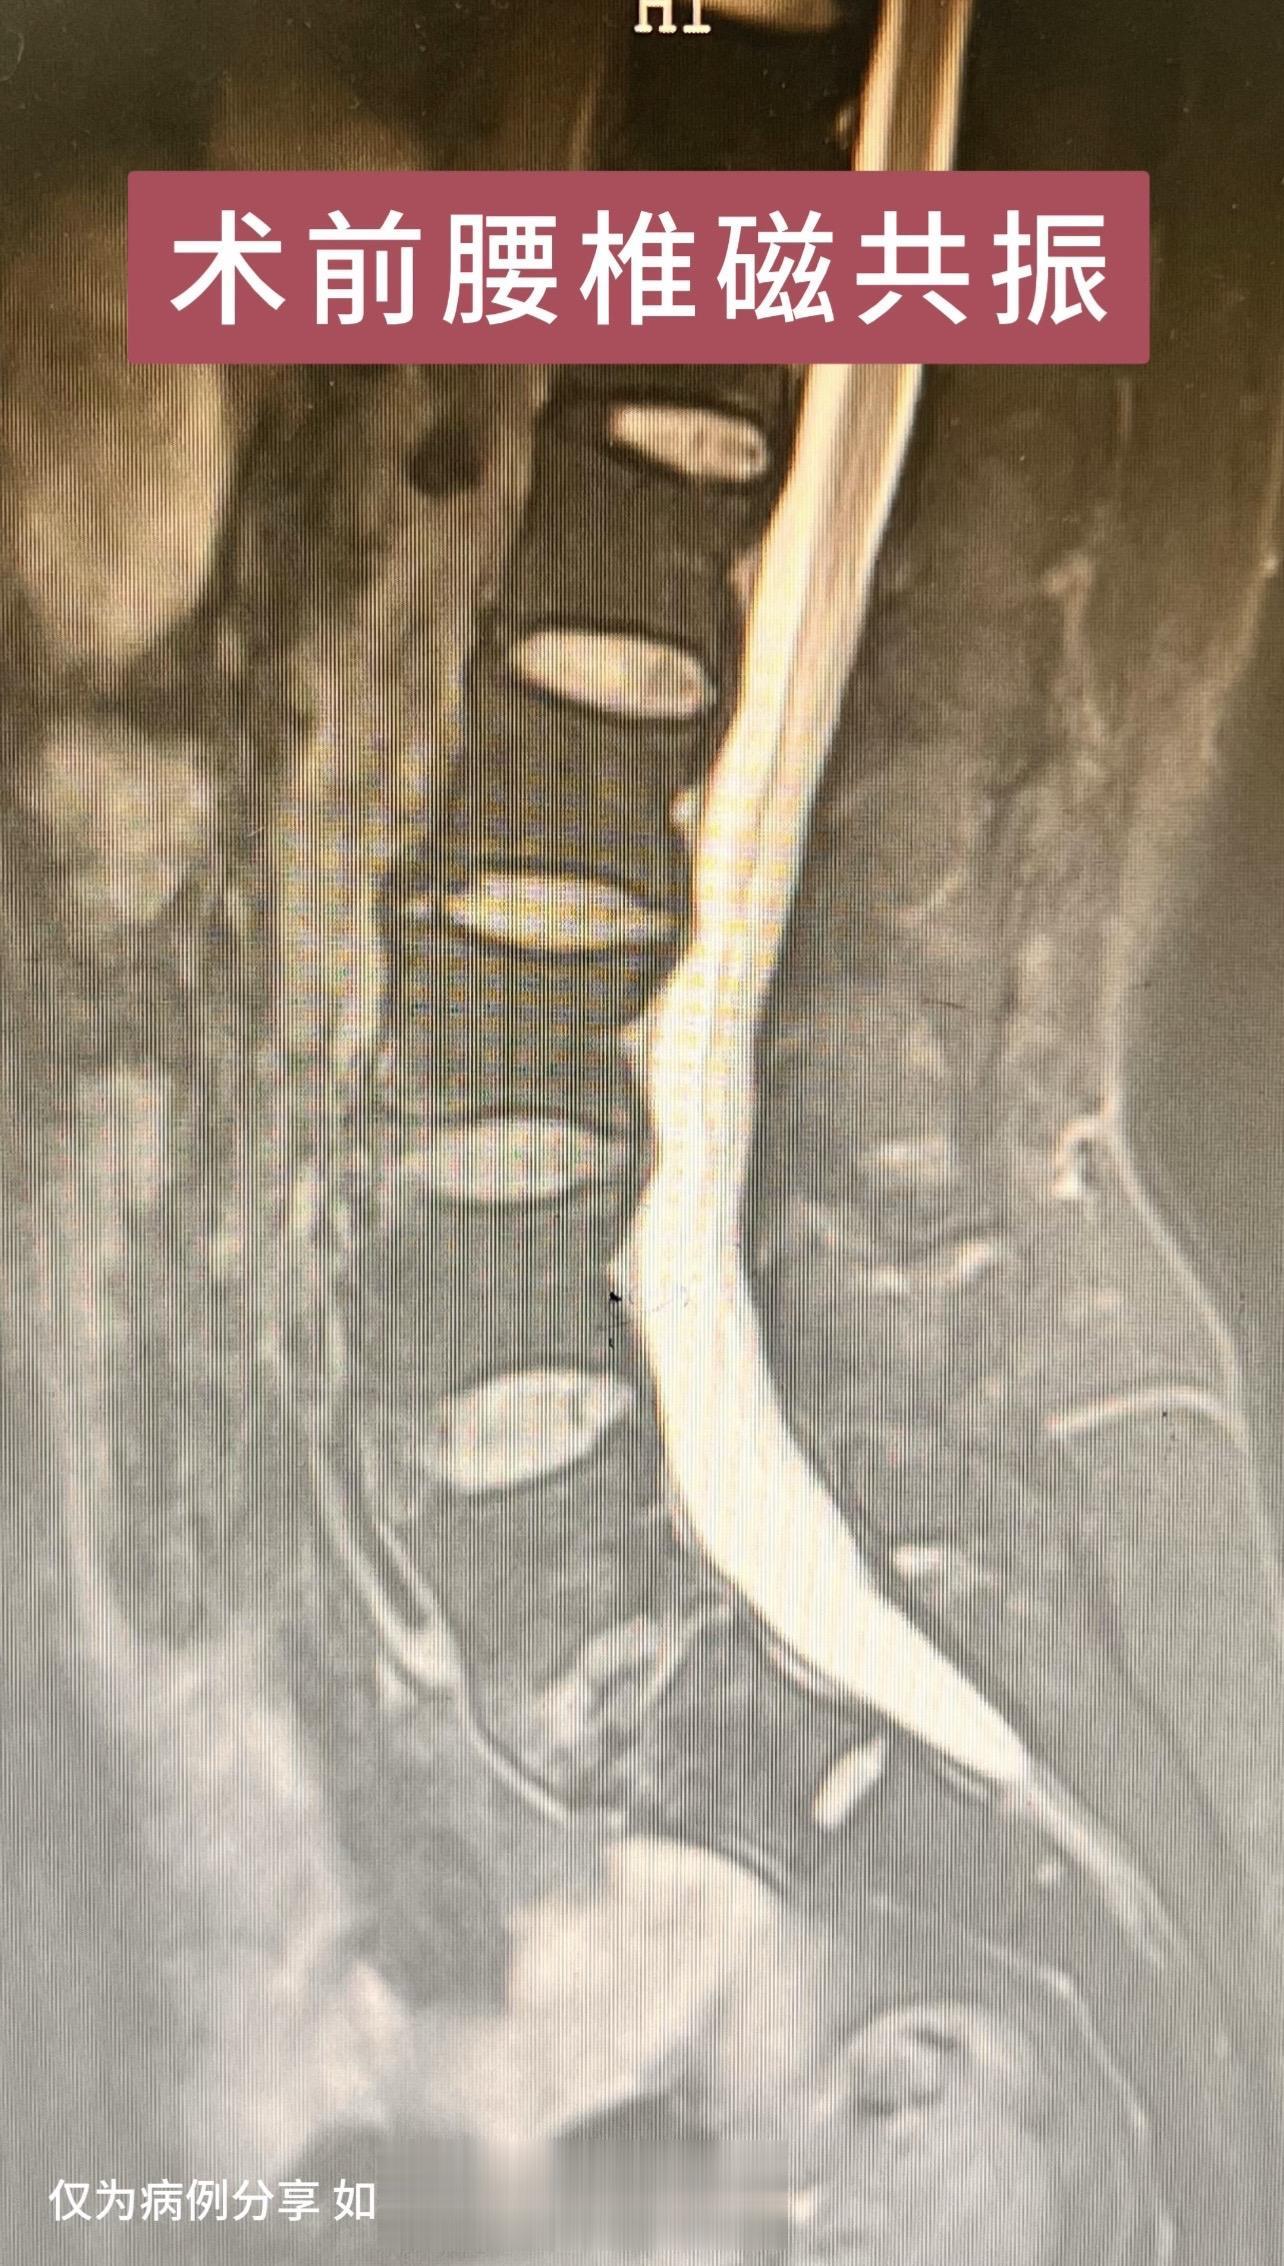

50岁女性,四肢麻木3年加重1年,双下肢重,偶有下肢踩棉花感。患者感觉很痛苦,看了好多医院,片子看着并不太重。2个月前在我科行保守治疗,效果差。后建议去北京协和会诊,协和说有手术指征,但不大。患者又返回我院,要求手术治疗,与患者沟通手术效果欠佳可能性大,但患者仍坚持手术治疗。术后患者双下肢麻木大大缓解,对手术效果十分满意。患者的理解信任是我们前进的动力源泉。